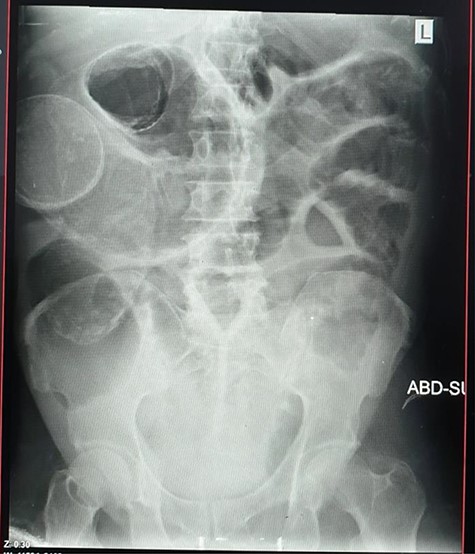

Radiological investigations

Plain abdominal X-ray (supine) showed grossly dilated large bowels (Fig. 1), and a chest X-ray showed a right-sided pneumothorax, which was managed by a thoracostomy tube (Fig. 2).

Abdominal ultrasound showed gaseous abdomen with dilated bowel loops, liver with course texture, heterogeneous margins, signs of portal fibrosis, minimal ascites and slightly splenomegaly.